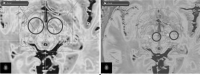

Images obtained from the DBS surgery planning station showing pre-operative (left) and post-operative (right) axial MRIs with an overlayed atlas for DBS of the STN